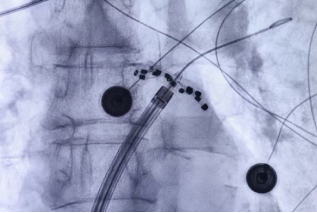

11月11日,我院院长助理、首都医科大学附属北京安贞医院安徽医院副院长、我院心血管内科学科带头人喻荣辉教授团队顺利完成安徽省首例FARAPULSE房颤脉冲消融(Pulsed Field Ablation, PFA)术。

PFA术是国内领先技术,通过施加高频电场脉冲使心肌细胞膜电穿孔,导致细胞程序性死亡,从而达到消除及阻止异常电位传递的目的。因不同组织细胞的电穿孔场强阈值不同,通过调节参数,脉冲电场消融可以实现心肌特异性消融,较为精确地消融靶向心肌组织,而不损伤毗邻组织。PFA的安全性有效性已获验证,优点在于能极大的缩短手术时间,减少传统导管消融并发症。喻荣辉教授介绍:FARAPULSE脉冲消融术的安全性和有效性已获循证医学支持,心脏穿孔等主要并发症显著减少,手术过程更加安全,治疗效果稳定。同时,术中消融过程左房操作平均时间约14分钟,手术时间显著缩短。